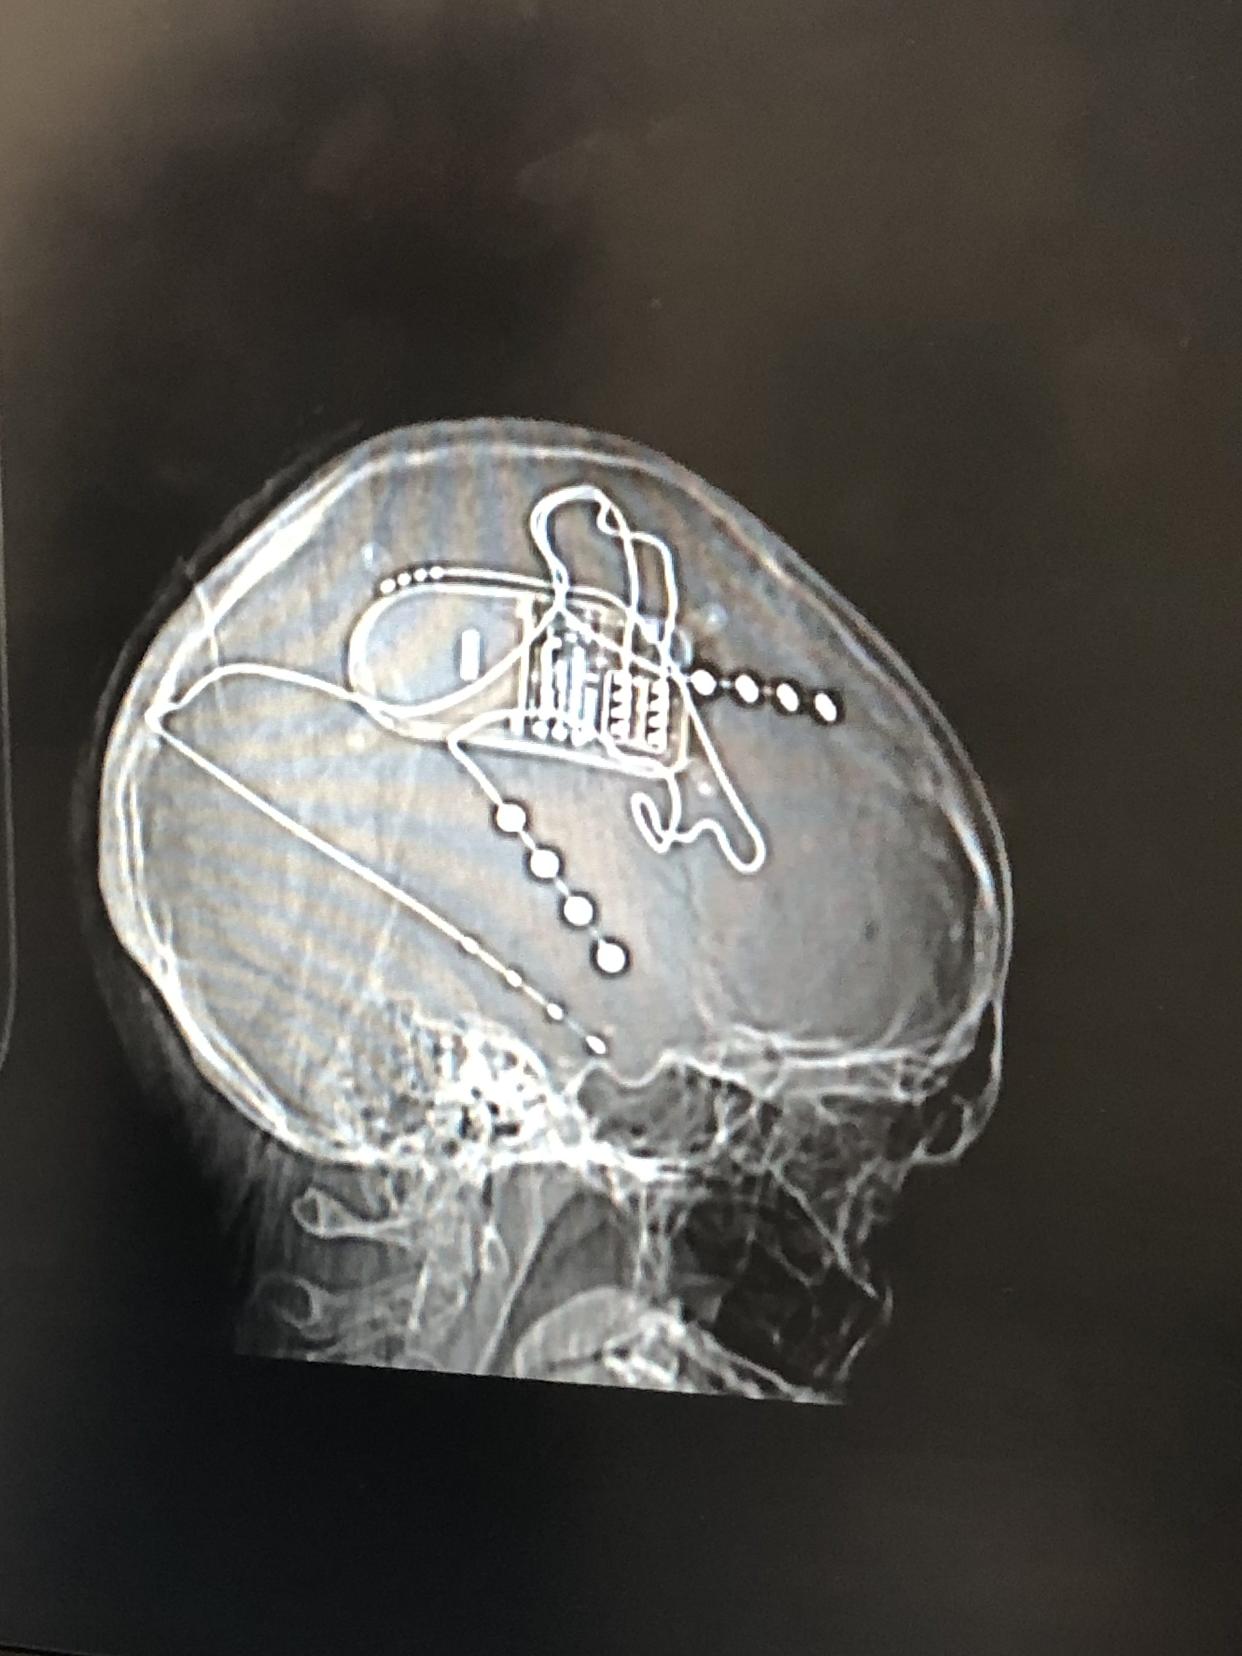

The device inside Hoffman’s brain. Courtesy of Arielle Hoffman

To stop the episodes, surgeons planned to implant a neurostimulation device — similar to a pacemaker — in Hoffman’s skull. Thin wires would be placed in the seizure-prone areas of her brain, detecting abnormal activity and delivering brief pulses of electricity to interrupt it.

The next step was stereoelectroencephalography (SEEG), in which surgeons drilled 14 small holes in her skull and placed sensors directly on her brain to see where the seizures were happening.

Finally, Hoffman underwent surgery to place the NeuroPace implant in September 2018, nearly two years after her first seizure.